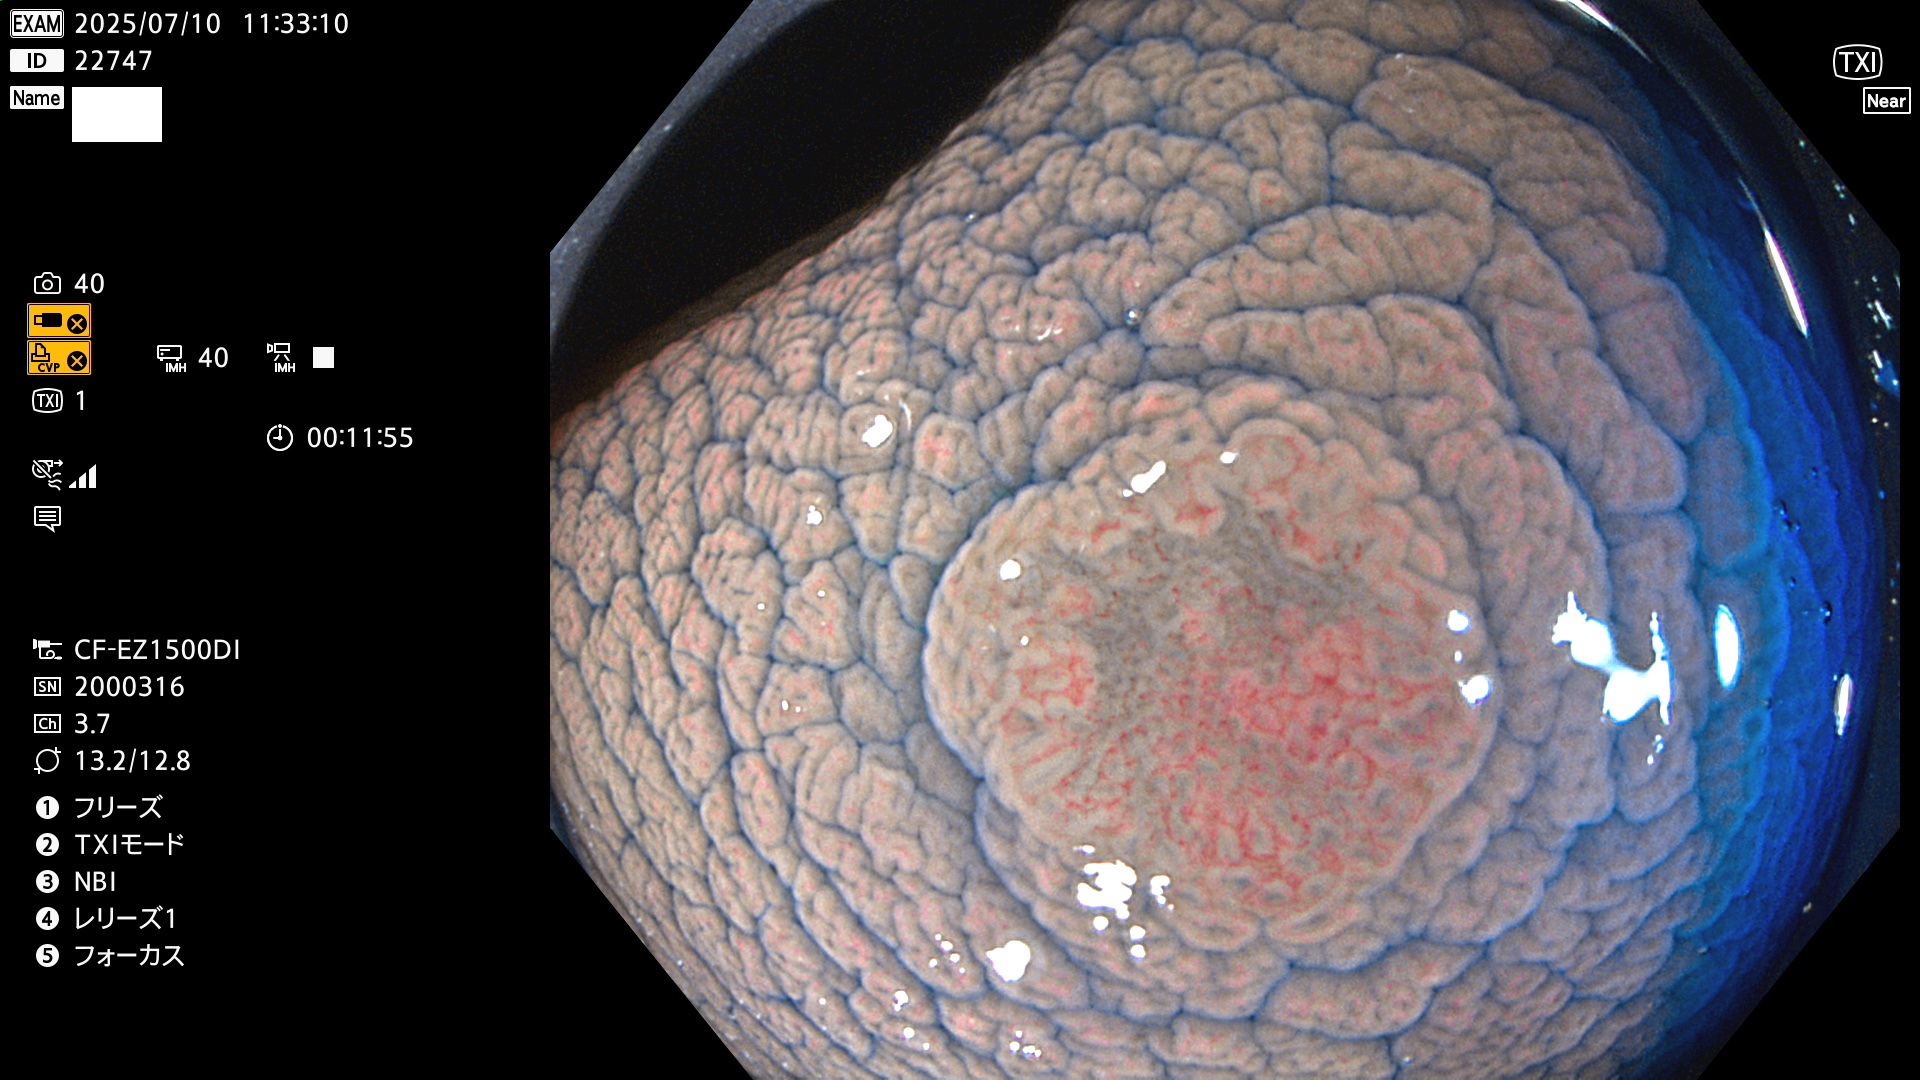

2025年7月10日〜7月13日の4日間(40件)15個 (Uc_ADR=15/40=38%)